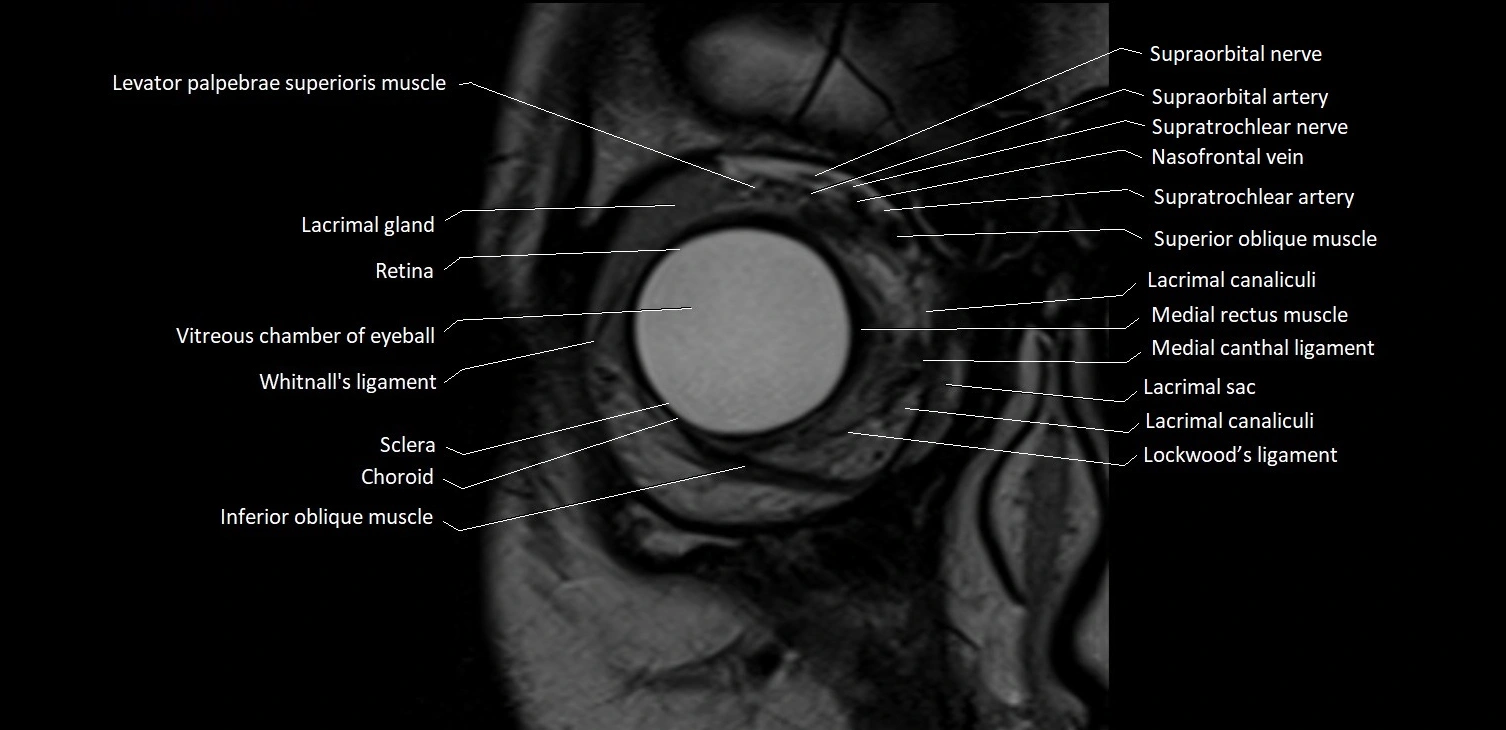

- Anterior chamber of eyeball

- Choroid

- Cornea

- Inferior oblique muscle

- Lacrimal canaliculi

- Lacrimal gland

- Levator palpebrae superioris muscle

- Lockwood’s ligament

- Medial canthal ligament

- Medial rectus muscle

- Retina

- Sclera

- Superior oblique muscle

- Vitreous chamber of eyeball

- Whitnall's ligament